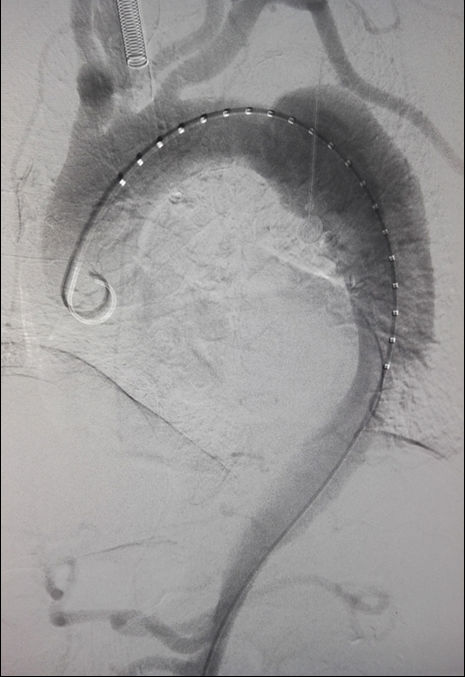

经血管主动脉夹层腔内隔绝术

腔内隔绝治疗主动脉夹层